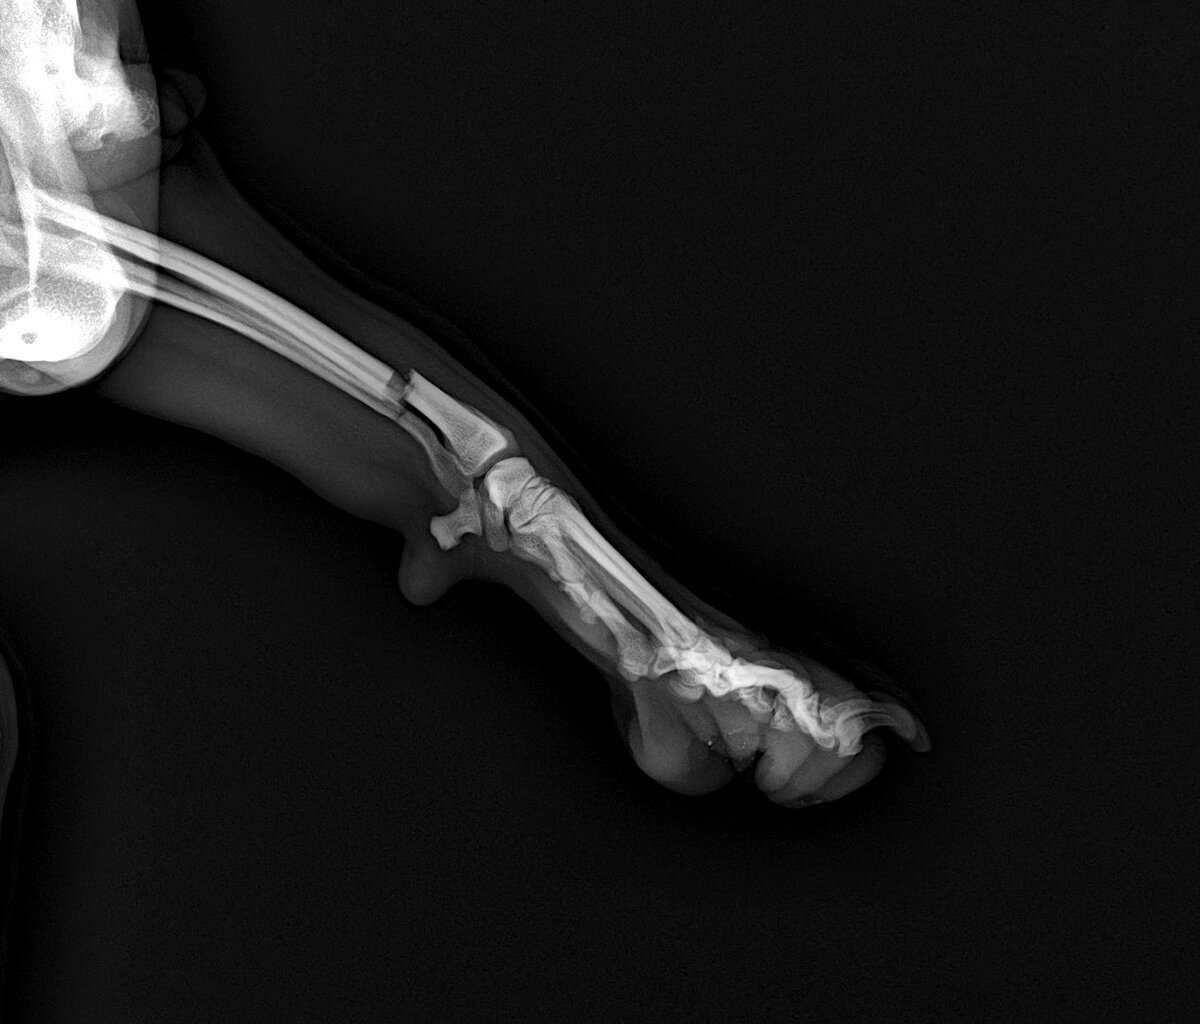

Перелом ... история умалчивает где и как ... Остеосинтез под общей анестезией ... пластина с семью винтами Как новая!

Остеосинтез под общей анестезией ... пластина с семью винтами